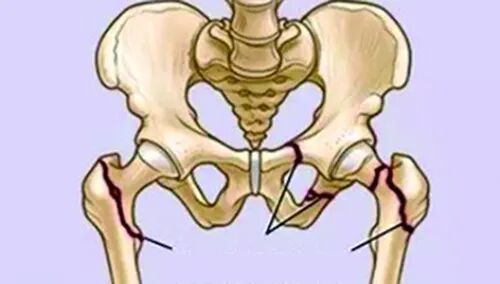

有人说髋骨骨折(臀部)相当于老年人的“死刑”,虽然听起来耸人听闻,但60岁以上的髋骨骨折患者,受伤后三个月的死亡率是同龄人的8倍。

图片

即使在致命的三个月后,仍然有大部分患者患有后遗症。许多老年人自此必须需要别人的日夜陪护。即便如此,风险也没有消除,第二次死亡高峰期是骨折后半年至一年之间。